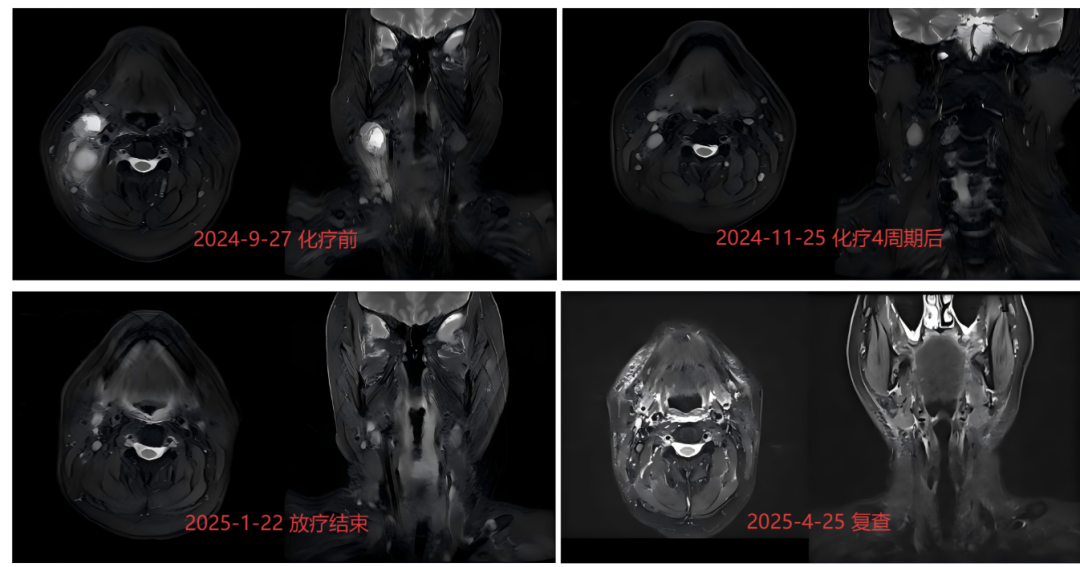

病例1:鼻咽癌治疗中的高适形性与低损伤

白先生(化名)在2024年9月确诊为鼻咽癌,低分化癌,经过4次化疗后达到部分缓解。

面对鼻咽位置深、周围要害器官众多且密集的挑战,TOMO放疗展现出了其高适形性的优势。通过螺旋CT扫描实时捕捉患者影像,TOMO放疗实现多子野照射,使高剂量区精准覆盖肿瘤,同时最大限度地减少对周围正常组织的照射。此外,TOMO放疗还能提供高剂量照射,并通过强度调节技术降低对腮腺、脊髓、脑干等敏感器官的损伤,从而提高鼻咽癌患者的生存率和生活质量。

其影像引导与自适应放疗功能,更是能在治疗过程中进行动态调整,确保每次照射的准确性,提高治疗的个性化和安全性。

治疗前后对比图